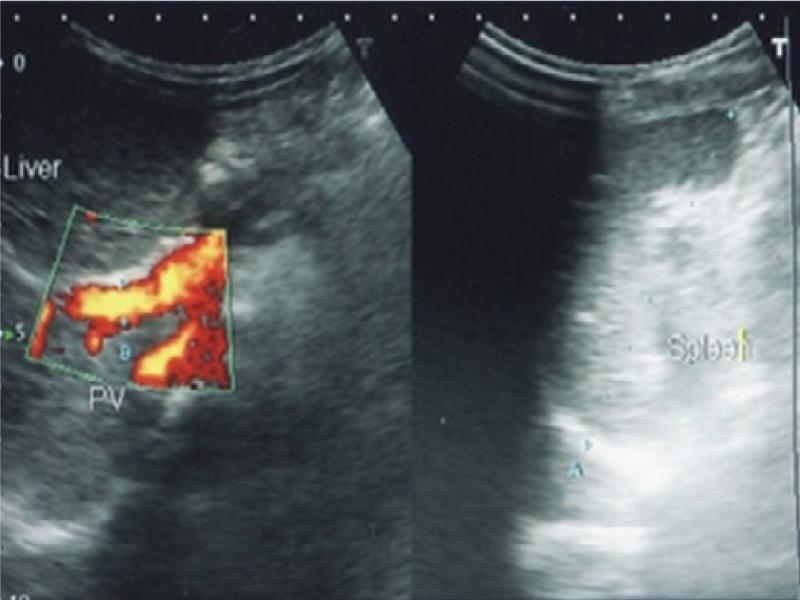

Fig. 4.